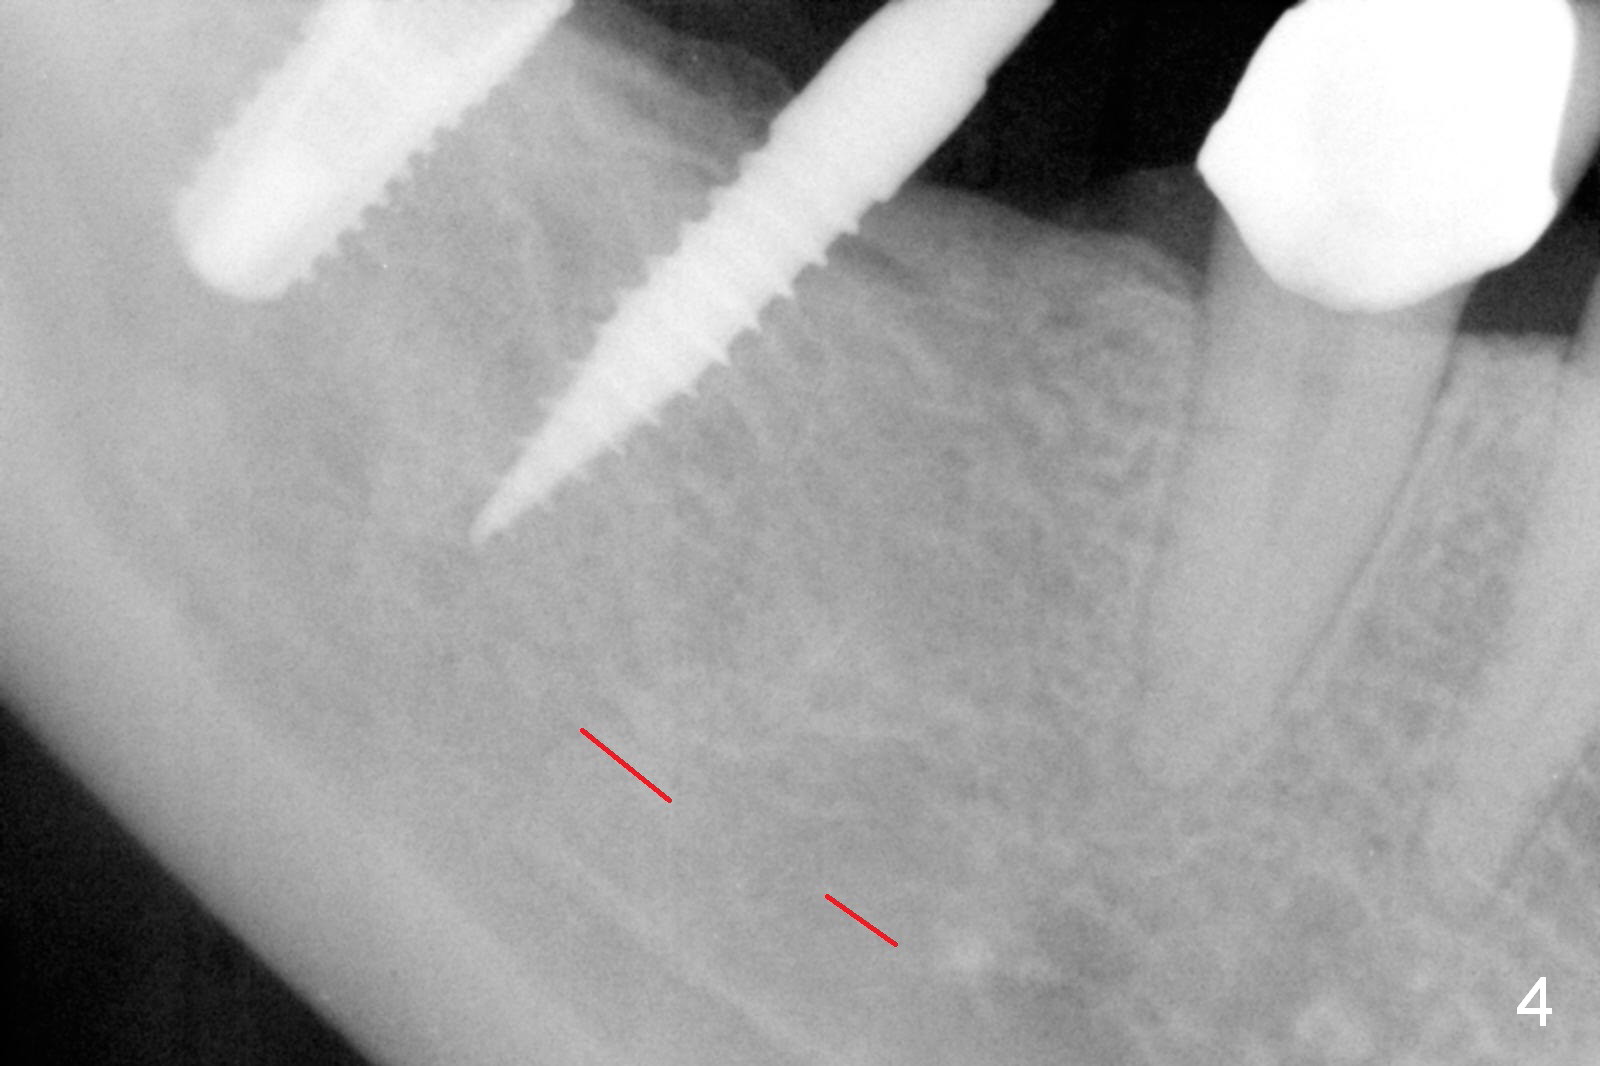

A preop photo shows different shape of pontics at #30 and 31 (Fig.1 <), suggesting different width of the edentulous ridge. Two of 8 mm parallel pins are inserted for position and trajectory (Fig.2 (red dashed line: the superior border of the Inferior Alveolar Canal). When they are removed from the osteotomy sites, the narrow ridge at #30 is shown (Fig.3). A 3x12 mm 1-piece implant is placed at #30, while a 4.5x10 mm 2-piece one at #31 (Fig.4,5). It appears that it is necessary to place an implant at #32, since the tooth #1 is present (Fig.5). The suggestion is rejected by the patient due to finance. After extraction of the tooth #32 and insertion of collagen plug, an immediate splinted provisional is fabricated to cover the #32 socket as well (Fig.6). The provisional is modified (to remove the portion that covers #32 socket) 3-4 weeks postop.